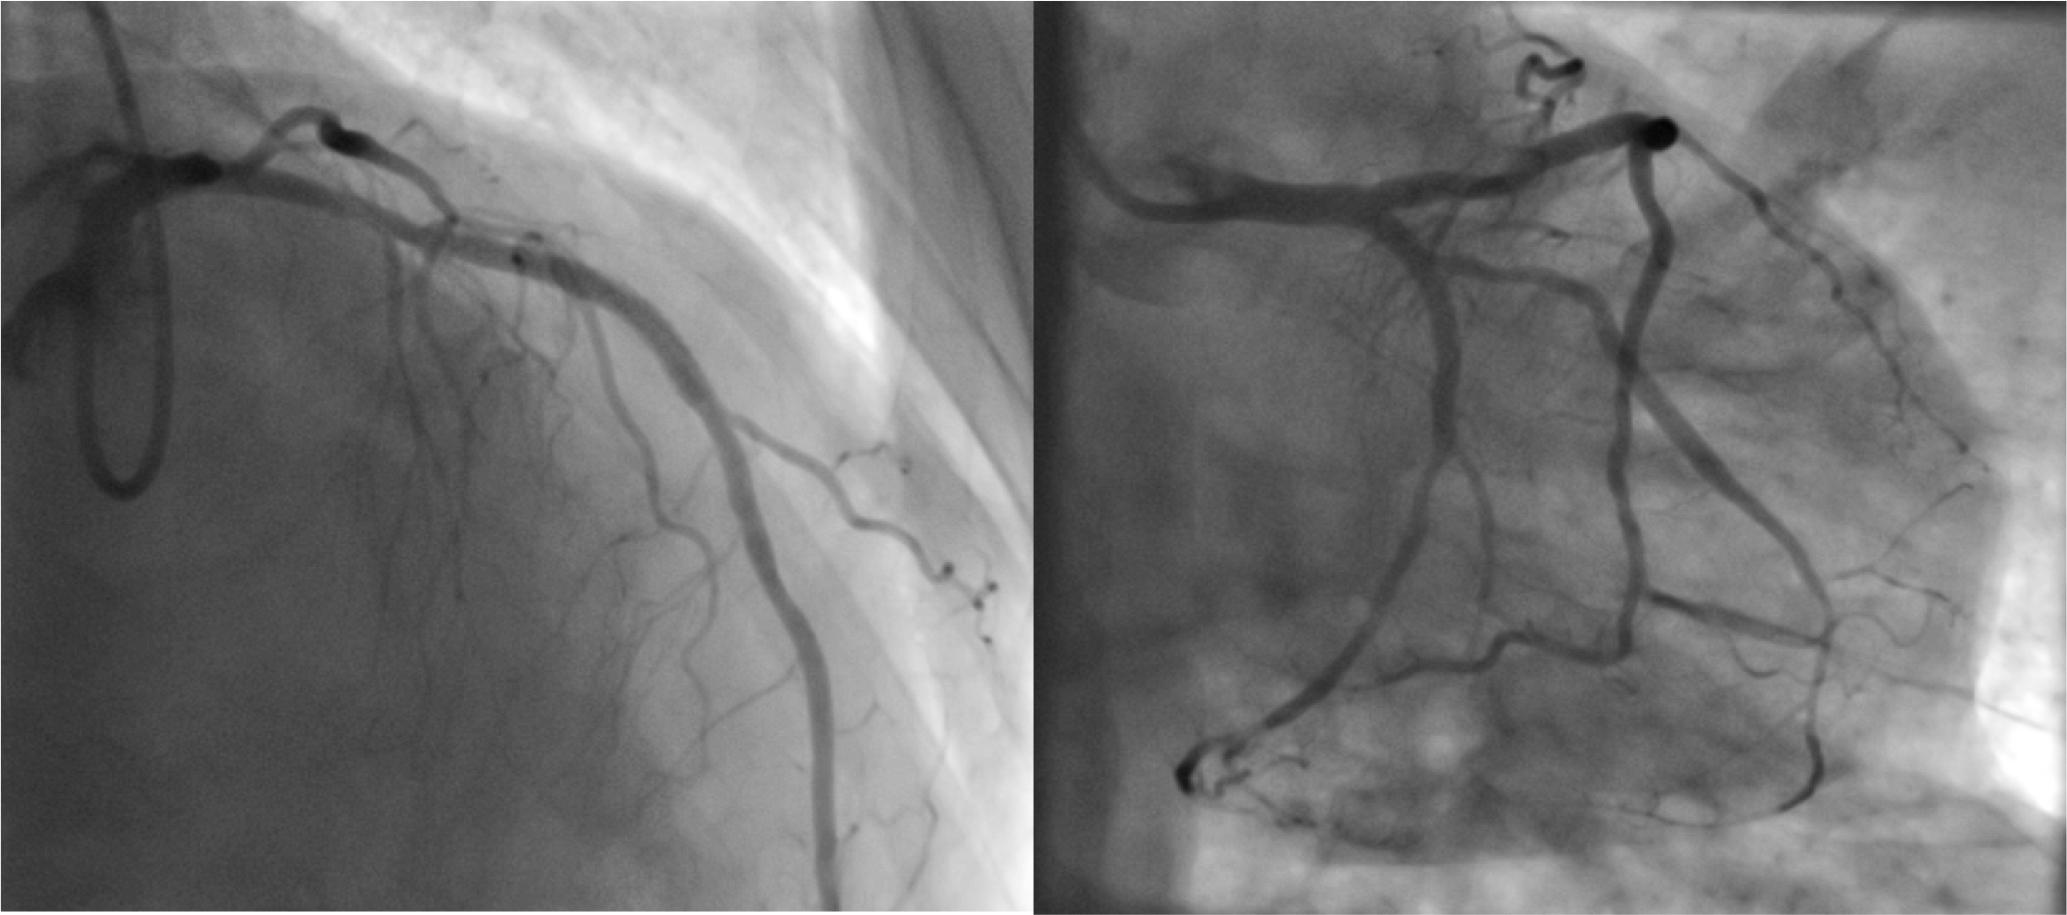

Coronary angiography revealed subocclusion of the middle segment of the obtuse marginal artery (OM1). The left anterior descending artery (LAD) exhibited a 50% stenosis in the middle segment that was deemed significant based on fractional flow reserve (FFR) measurement. Additionally, the proximal segment of the left circumflex artery (LCx) showed a 50-60% stenosis, which was also determined to be hemodynamically significant based on FFR. Coronary angioplasty was performed with three drug-eluting stents in the middle LAD, proximal LCx, and middle OM1. (Fig. 2A and Fig. 2B)

Coronary angiogram after implantation of 3 drug-elluting stents (middle LAD, proximal LCx and middle OM1)